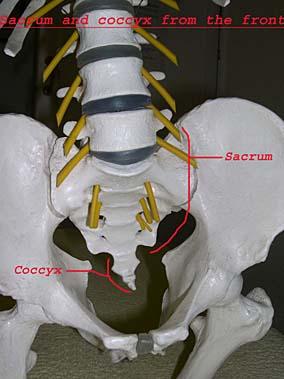

The coccyx is at the very bottom part of the spine, and consists of four or more very small bones stuck together. The coccyx initially joins with the sacrum through a small disc, and is also connected to the sacrum and pelvis with ligaments. In the coccyx, the vertebrae generally fuse together in early adulthood and may also fuse with the sacrum. It is not clearly understood which part of the coccyx causes pain; probably the ligaments or the joint cause the pain.